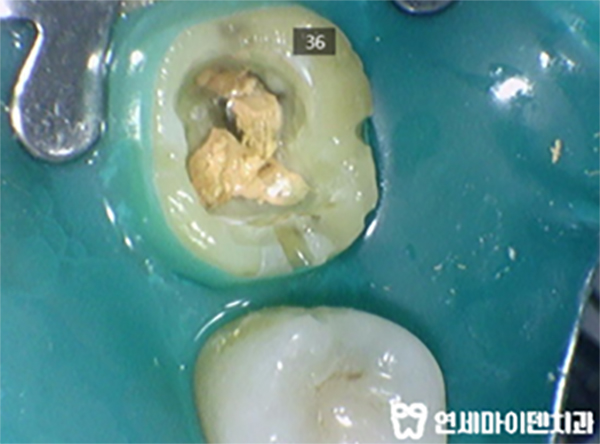

이 환자분도 어금니 2개를 모두 뜯어보았습니다.

어떤가요?

치과 의사나 치과에서 일하는 전문인이 아니더라도

이건 누가봐도 문제가 있어 보이죠?

신경치료 실패 원인은 밀폐가 제대로 되지 않아서입니다.

신경치료 후에는 코어 밀폐를 제대로 해야 세균오염이 되지 않는데,

이 분은 신경치료 후 '임시재료'로 메워놓았네요 ㅜㅜ

온도에 민감한 증상이 생겨버렸습니다 ㅠㅠ

더 깊이 신경관으로 접근해보았습니다.

제대로 밀폐가 되어 있지 않는바람에 내부 오염이 심한 상태입니다.

신경관을 제대로 찾아주고, 제대로 밀폐를 하는 재치료가 시급합니다.